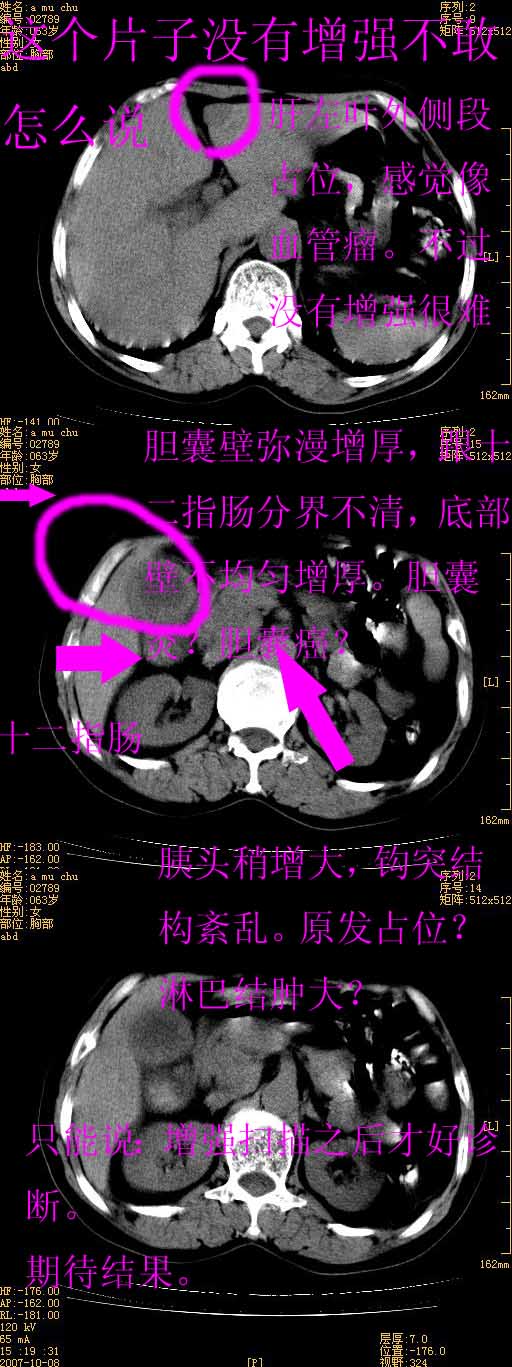

以下是引用卜一在2007-10-17 19:12:00的发言:[br]无增强,很难说!高度可疑:胰头癌?胆囊病变?肝左叶占位?

以下是引用王维浦在2007-10-17 21:02:00的发言:[br]胆囊增大,囊壁明显不规则增厚,邻近肝组织浸润,肝内外胆管无扩张。诊断:胆囊ca;[br]胰头软组织肿块影,考虑是由转移肿大的胰后淋巴结、没有肠道准备的十二指肠及胰头共同形成。[br]

以下是引用zhangzexing在2007-10-18 7:13:00的发言:[br]支持胰头占位,慢性胆囊炎. 2.肝左叶前外侧段占位,血管瘤?建议增强

以下是引用影像实习生在2007-10-17 19:49:00的发言:[br]支持胰头占位,慢性胆囊炎. 2.肝左叶前外侧段占位,血管瘤?建议增强.

以下是引用刘振江在2007-10-17 19:42:00的发言:[br]没有增强,胰头癌?胆囊及肝左叶占位?